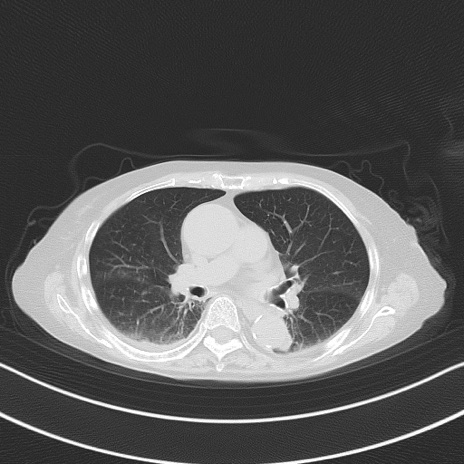

症例40(横断像)他院1日前

横断像

他院CT